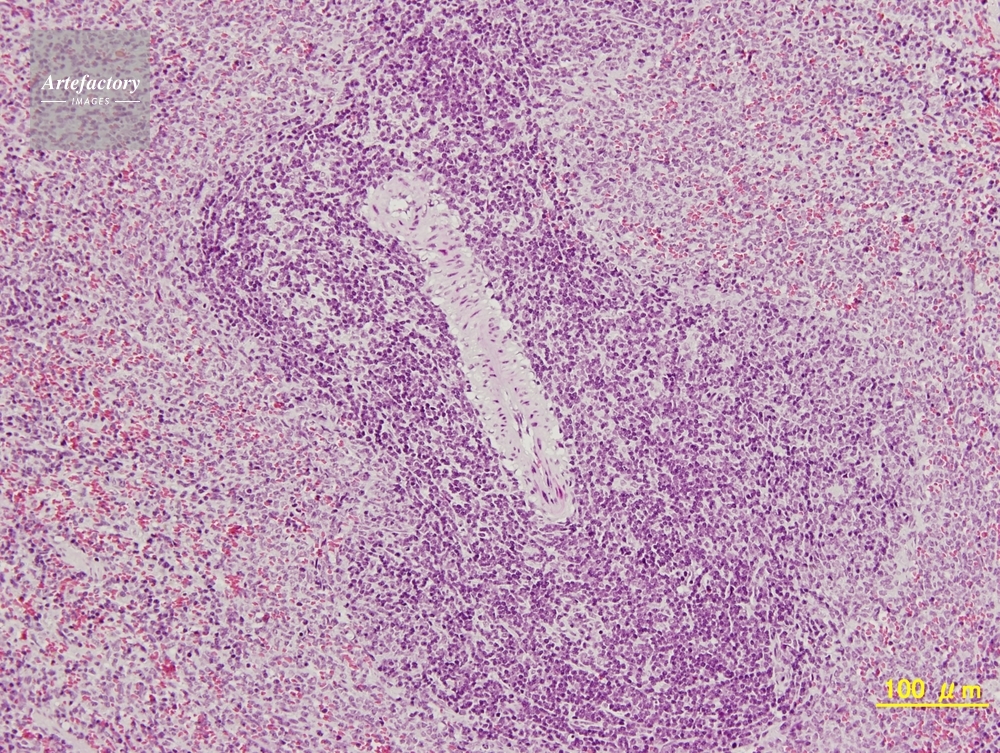

| 作品タイトル | マウス,脾臓 | モデルリリース | なし | |

| 作家 | OLYMPUS CORPORATION Technolab | プロパティリリース | なし | |